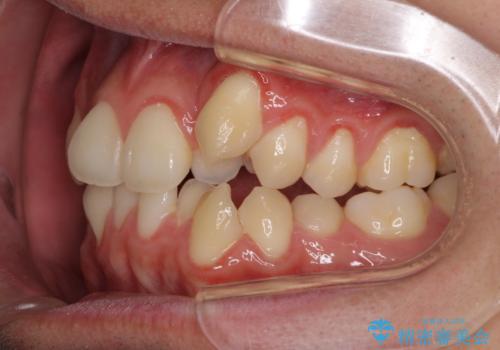

- 上下の八重歯や乱杭歯を気にして来院され患者様です。

スペースを確保するため、上下左右の小臼歯を抜歯し、ワイヤー装置に矯正することとしました。

奥歯の咬み合わせの左右差が大きかったため、変則的な抜歯矯正を行いました。

治療期間はやや長期化しましたが、満足のいく歯並びとなりました。